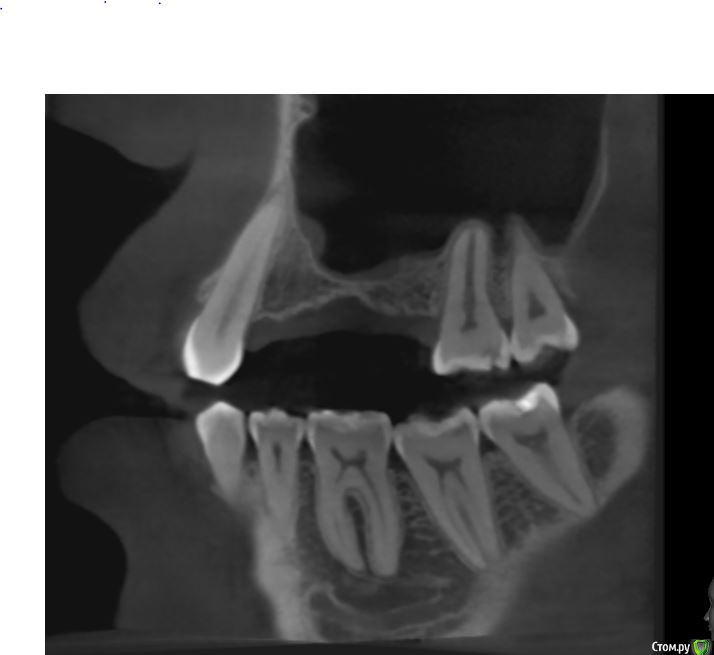

jm3300 Опубликовано 12 июля, 2016 Автор Поделиться Опубликовано 12 июля, 2016 А до операции КТ могли бы выложить? И сколько времени отсутствовали зубы в этой области?отсутствовали достаточно долги. КТ до: Ссылка на комментарий

jm3300 Опубликовано 14 июля, 2016 Автор Поделиться Опубликовано 14 июля, 2016 выкладываю кт Ссылка на комментарий

умножающий печаль Опубликовано 14 июля, 2016 Поделиться Опубликовано 14 июля, 2016 Промыть пазуху через соустье, курсом. Я отправляю к ЛОРам. Антибиотикотерапия, гипосенсибилизация. Один из винтов вестибулярно без костной поддержки, на мой взгляд. 1 Ссылка на комментарий

red_butler Опубликовано 15 июля, 2016 Поделиться Опубликовано 15 июля, 2016 Пазуха чистая, Антон, какой винт на выход не понял?Может у пац аллергия ?На последних срезах, вестибулярно на 2/3 кости нет.Какая уж аллергия, если боль и отек 1 Ссылка на комментарий

умножающий печаль Опубликовано 15 июля, 2016 Поделиться Опубликовано 15 июля, 2016 Тоже не понял, вроде все хорошо стоят. Главное слизистые то в покое.Это пока в покое. Винт не покрытый костью, долго под мягкими тканями оставаться не будет. Неизбежна рецессия со всеми вытекающими. 1 Ссылка на комментарий